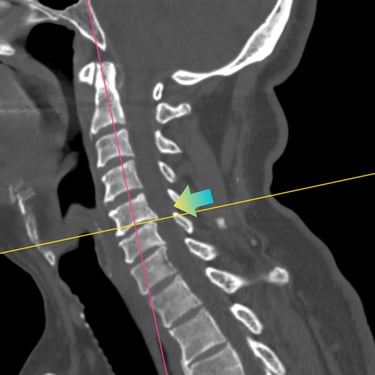

Hernia Cervical con Mielopatía: ACDF con Cage y Placa asistida con Monitoreo Neurofisiológico

La hernia cervical con mielopatía se produce por la compresión de la médula espinal, ocasionando dolor cervical, debilidad, alteraciones sensitivas y trastornos de la marcha. En casos de compromiso neurológico progresivo, la discectomía cervical anterior y fusión (ACDF) con cage y placa es una alternativa quirúrgica eficaz. La cirugía asistida con monitoreo neurofisiológico intraoperatorio permite evaluar en tiempo real la función neurológica, aumentando la seguridad del procedimiento. Este abordaje facilita una descompresión adecuada, estabilización del segmento cervical y favorece una recuperación neurológica segura y progresiva.